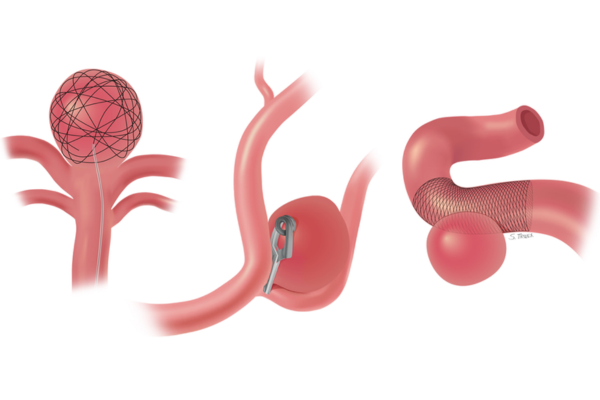

Supports coil placement in complex aneurysms, ensuring safe sealing.

Seals aneurysms internally without stents, preserving normal blood flow.

Provides support for wide-neck aneurysms, ensuring secure coil placement and safer, more effective treatment.

Enhances treatment by redirecting blood flow away from the aneurysm, promoting gradual healing, improving vessel stability, and ensuring stronger, durable protection against future rupture.

Placed directly inside the aneurysm sac, these devices offer targeted treatment with minimal vessel manipulation for improved safety.

Stent or balloon assisted coiling is used for wide-neck brain aneurysms where simple coiling is unsafe or insufficient. These techniques support the aneurysm neck during treatment.

They help keep coils securely in place, prevent coil movement, and improve long-term aneurysm sealing safely.

Intrasaccular devices are placed directly inside the aneurysm sac to block blood flow at its origin. They are useful for select wide-neck aneurysms.

These devices seal the aneurysm internally without affecting the parent artery or surrounding brain circulation.